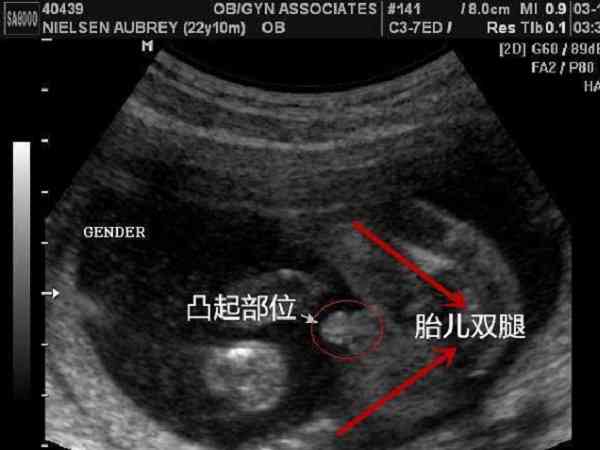

懷孕3個月的b超圖片怎麼分辨生男生女?

懷孕3個月的b超圖片主要是通過胎兒的性器官來判斷生男生女的,不過懷孕3個月的時候,胎兒的性器官才剛剛開始分化和發育,這時候通過性器官來判斷胎兒的性別可能會出現較大的誤差,通常情況下b超單上有三條明顯的白線,白線比較明亮,說明生女孩的可能性,... 全文